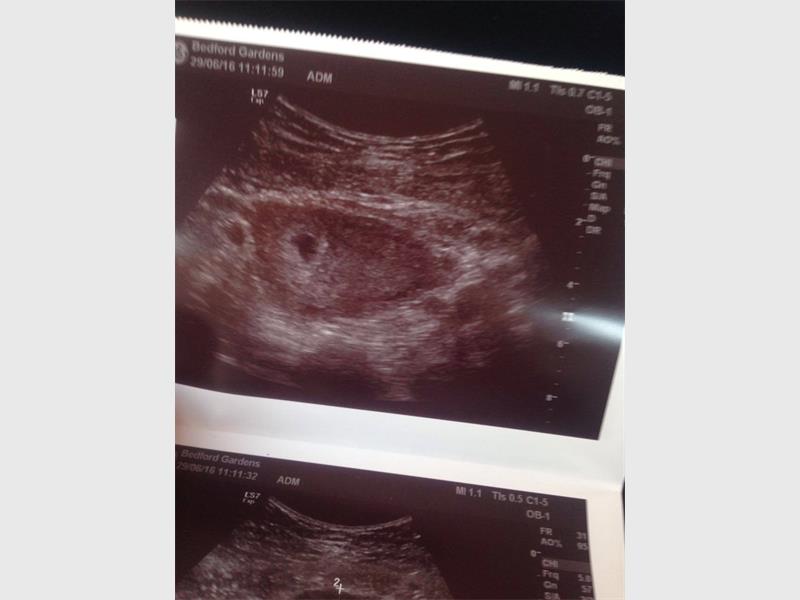

They went to the doctor on June 29 and it was confirmed. Hayley was born on April 4 weighing around 600g, but after two weeks of fighting for her life, she lost the battle on April 18.